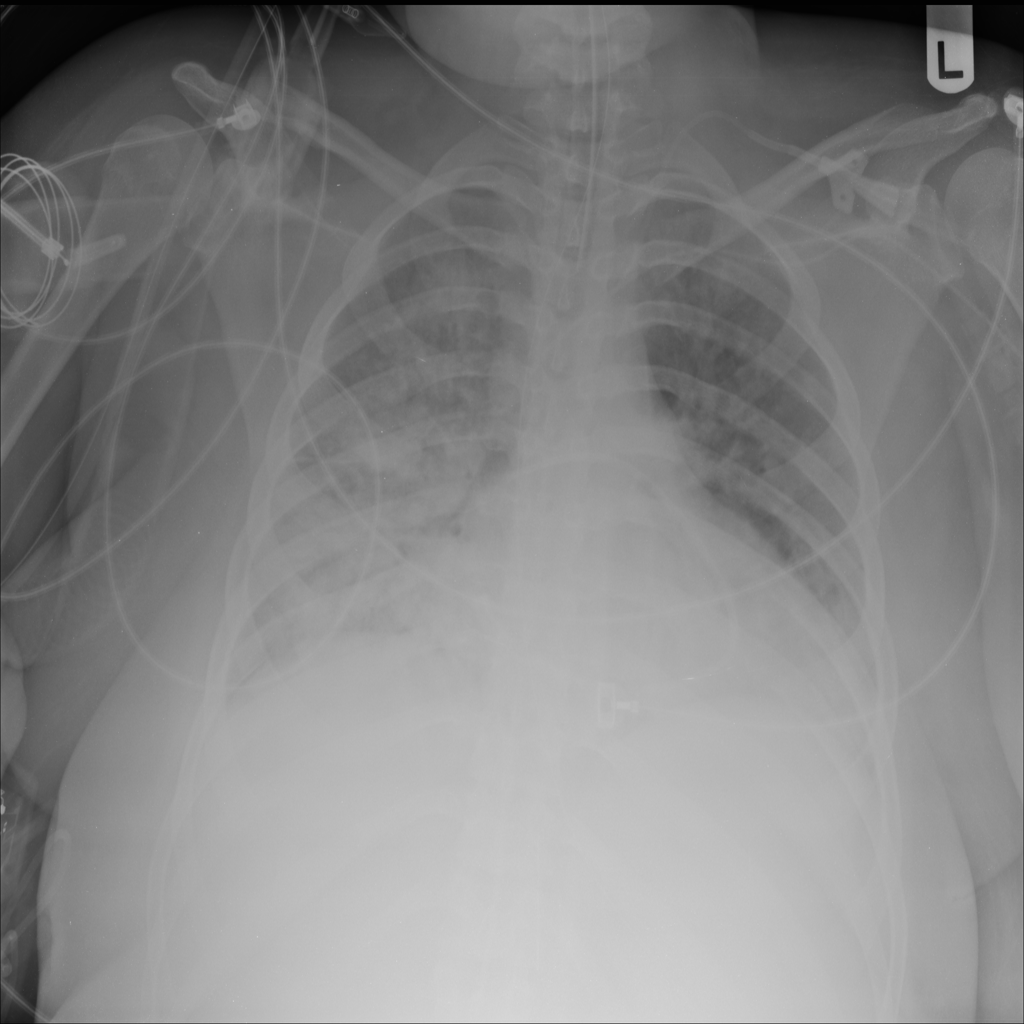

PAT-24D9 · IMG-006Edema

PAT-24D9 · IMG-006

AP